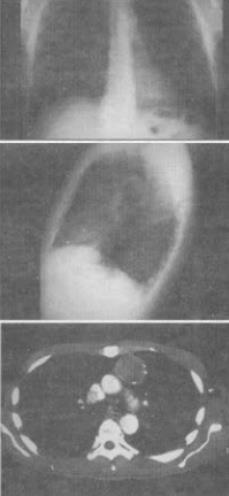

患者男,47岁,腹泻、体重下降,伴有重症肌无力,结合胸片和CT,最可能的诊断是()。

A、胸腺增生

B、胸腺瘤

C、淋巴瘤

D、纵隔血肿

E、错构瘤

正确答案:

B